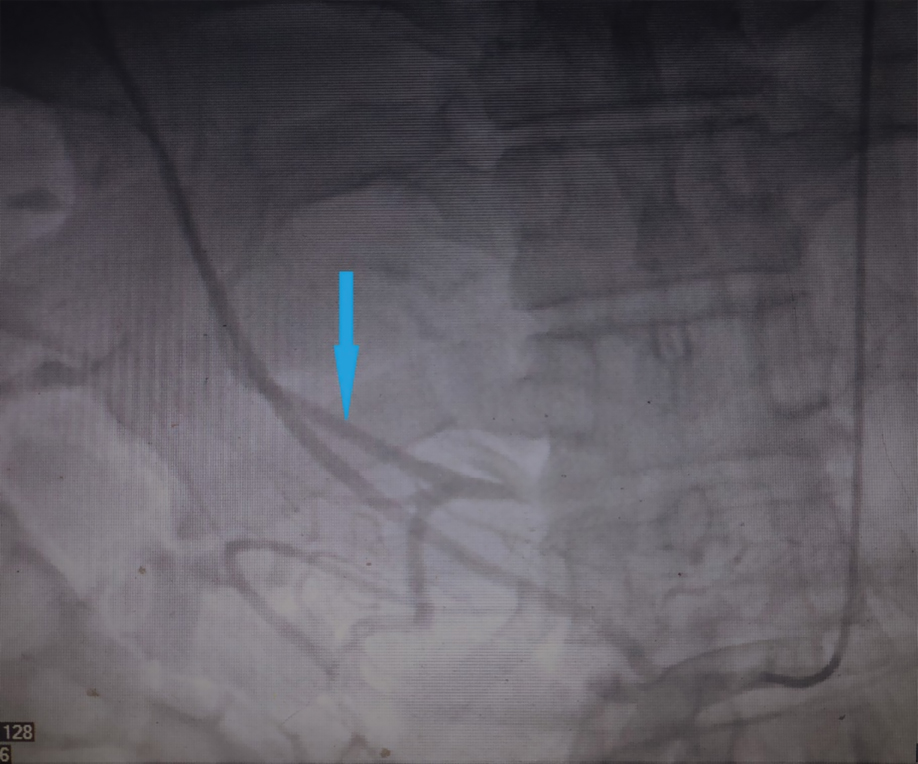

Cell technologies in the form of injecting autologous mesenchymal stem cells in an amount of 25x106 into the liver arterial bed were used to treat this patient. In a hospital setting, the patient was injected autologous mesenchymal stem cells into the liver arterial bed (Figure 1).

Рисунок 1. Целиография и мезентерикография пациента А. Стрелкой обозначена правая печеночная артерия, в которую вводились аутологичные мезенхимальные стволовые клетки.

Figure 1. Coeliography and mesentericography data of patient A.

The arrow indicates the right hepatic artery where autologous mesenchymal stem cells were implanted.